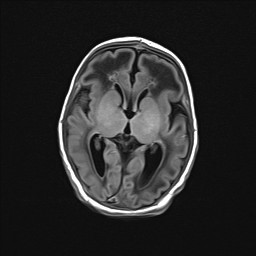

En el corte axial de la RM cerebral (Fig. 1C y 1D) se aprecia un aumento de señal de sustancia blanca con una ventriculomegalia y un quiste de septum enorme.

Figura 1D. RM cerebral. Corte axial en T2-WI.